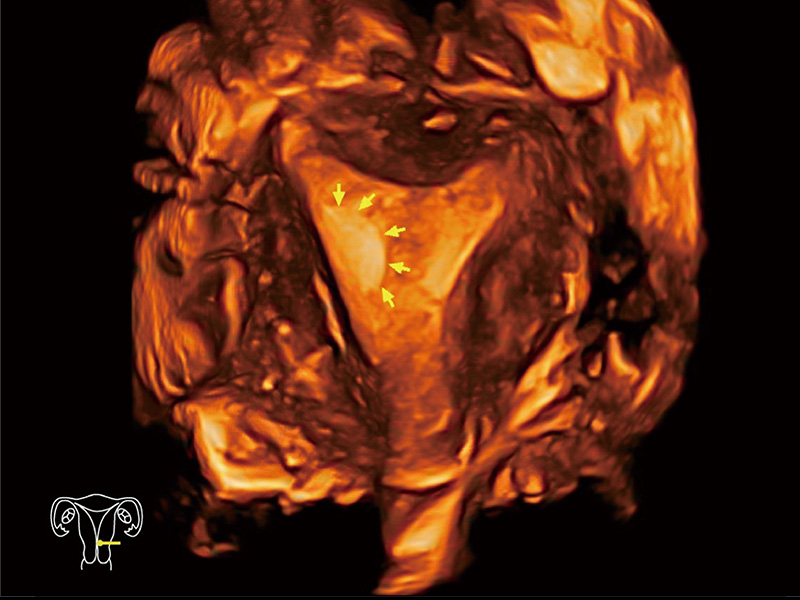

“生育问题”即关系民族复兴,也关系亿万家庭的幸福。随着婚育年龄推迟、社会压力增加等因素,越来越多人群也面临着“生不出、生不好”的问题。辅助生殖作为治疗不孕不育最有效的方法之一,也逐渐成为育儿新希望。而超声检查能为生殖需求人群的初诊评估提供宝贵的信息。 P20 Elite是开立医疗匠心打造的一款生殖应用型彩超。她继承开立医疗高端极光平台,突破性地将多款新型芯片及硬件模块进行整合,均衡了高端系统性能与小巧灵动机身。P20 Elite卓越的图像质量搭载专科探头,旨在为您提供全面的辅助生殖解决方案。

P20 Elite配备了丰富的生殖探头群和临床应用功能,在卵泡监测、穿刺取卵、胚胎移植、妊娠确认等领域,为生殖需求人群提供了新的临床机会,重新定义高端超声如何应用于生殖健康检查。